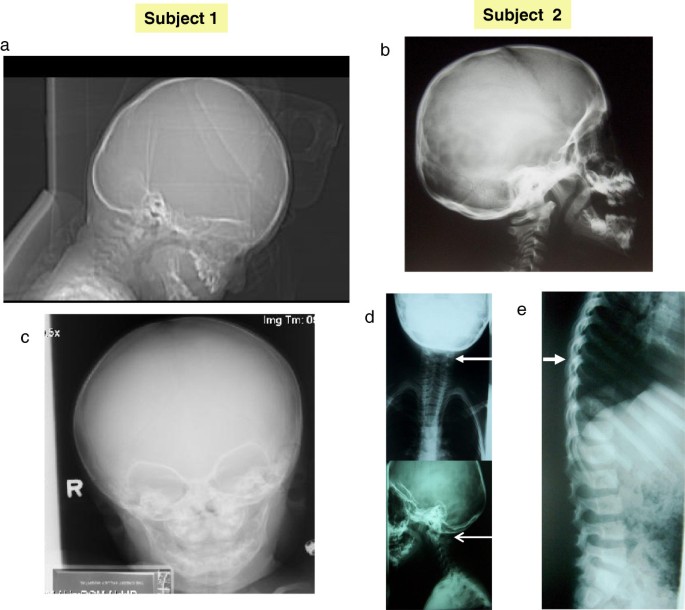

Chromosome testing was normal, including FISH at 22q11.2. A CT scan of the brain was normal. Skull radiographs at age 7 months showed a shortened anterior-posterior diameter relative to width. There was slight asymmetry of the appearance of the orbits, with the left side a little larger and slightly more prominent superiorlaterally (Figure 2). No obvious sutural stenosis was evident. At age 14, a C-spine radiograph was normal.

At four years, his growth parameters were normal (weight: 75th percentile; height: 50-75th percentile and OFC: 50-75th percentile). At five years he had a global developmental quotient of 53.4 on the Griffiths Mental Developmental Scale evaluation. His I.Q. at the age of 7 years based on the Wechsler Intelligence Scale was 73 (borderline mental retardation), with a verbal scale of 66 and performance scale of 89. The proband was dysmorphic with a triangular face, brachycephaly, hypertelorism, up-slanting palpebral fissures, thin lips, hypertrophic gums, a pointed chin and short neck (Figure 1). He had abnormal ears (asymmetric, dysplastic and low-set). The right ear was small, cup-shaped, anteverted and the lobule was hypoplastic. The left ear was bigger than the right, with a thick helix. Asymmetry of the jaw was noted, with the left side longer than the right side. His fingers were slightly tapering. Radiographs revealed congenital C1-C2 vertebral fusion, with accentuation of dorsal kyphosis (Figure 2).

We report a 2p13.1-p13.3 microdeletion observed in two subjects with clinical effects on the cognitive function (ID and language delay), behaviour (hyperactivity), and development of the craniofacies (facial asymmetry, unusually shaped and asymmetric ears and brachycephaly). Skull and vertebral bone abnormalities included slight asymmetry of the appearance of the orbits and delayed closure of the metopic suture in Subject 1 and congenital C1-C2 vertebral fusion, and accentuation of dorsal kyphosis in Subject 2. Previous cases with cytogenetic deletions/disruptions of this region all had developmental delay and the majority had head/facial anomalies, ear and skeletal abnormalities [1, 2].